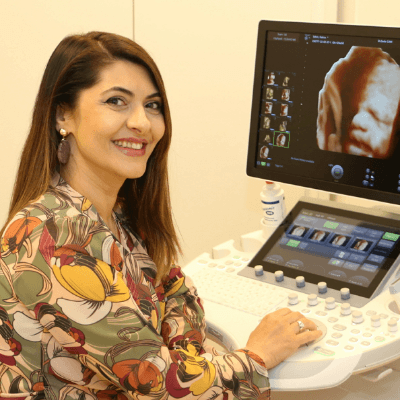

Associate professor OB/GYN Zagazig university, Egypt